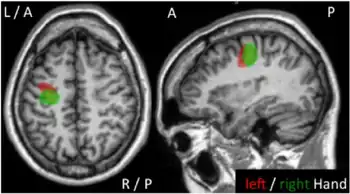

Epilepsia partialis continua is a rare[1] type of brain disorder in which a patient experiences recurrent motor epileptic seizures that are focal (hands and face), and recur every few seconds or minutes for extended periods (days to years).